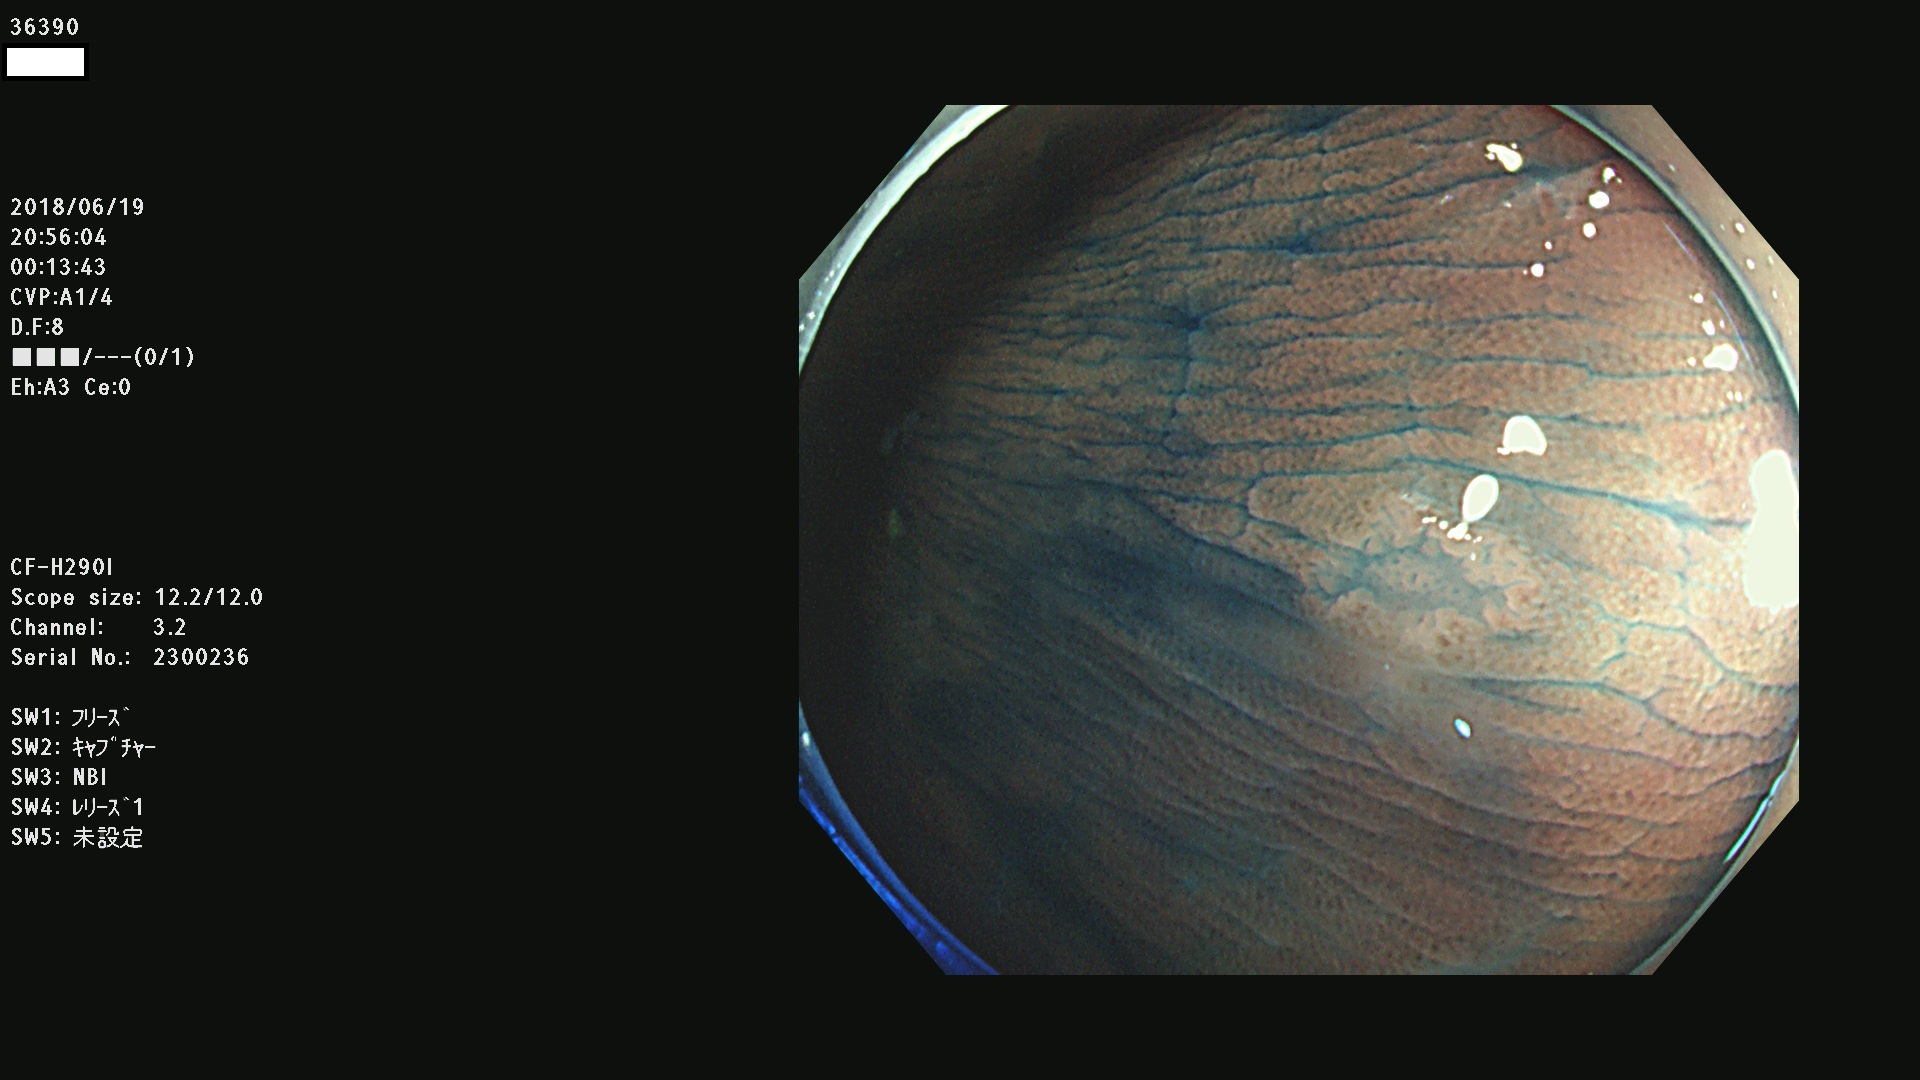

発見困難で危険性の高い平坦型病変(上記100名より抽出) ![]()